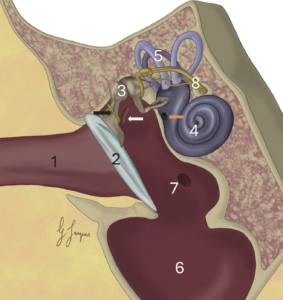

Colgajo axial insular auricular caudal en un gato para reconstruir un defecto facial tras la resección oncológica de un mastocitoma cutáneo

Este tipo de colgajo se utiliza en gatos para la reconstrucción de heridas en el cuello, el dorso de la cabeza y la oreja, así como para defectos que afectan al párpado superior, al área frontotemporal y a la región